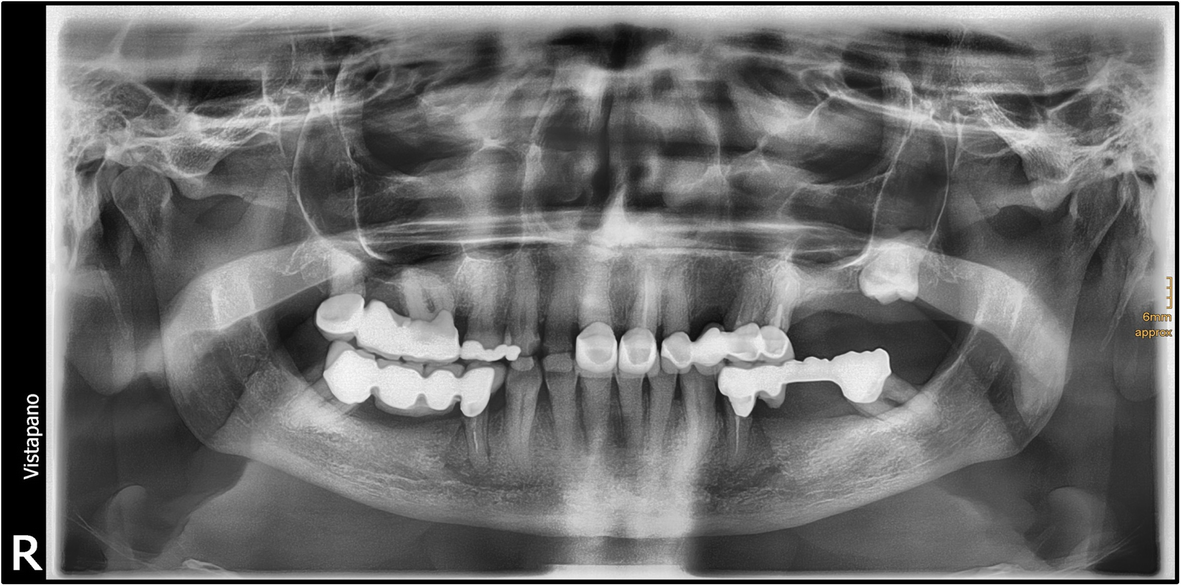

Abscess Lymph Node Neck. there are several types of neck abscesses that are found in children, including the following: Interpret the signs and symptoms that patients with a neck abscess may exhibit. superficial neck abscesses are usually the result of an infection in a lymph node in the neck (lymphadenitis) turning into an. Infections of the lymph nodes in the neck can lead to the formation of abscesses. Determine which patients are most at risk for developing. swollen lymph nodes in the neck can affect children and adults of all ages. lymph node infections: deep neck space infections most commonly arise from a septic focus of the mandibular teeth, tonsils, parotid gland,. a retropharyngeal abscess is a swelling in the neck caused by an infection. It is most often caused by bacteria that can multiply and create a pocket of infection in the interior lymph nodes of the neck. The swelling is usually temporary and harmless.

Infections of the lymph nodes in the neck can lead to the formation of abscesses. superficial neck abscesses are usually the result of an infection in a lymph node in the neck (lymphadenitis) turning into an. a retropharyngeal abscess is a swelling in the neck caused by an infection. swollen lymph nodes in the neck can affect children and adults of all ages. deep neck space infections most commonly arise from a septic focus of the mandibular teeth, tonsils, parotid gland,. there are several types of neck abscesses that are found in children, including the following: Interpret the signs and symptoms that patients with a neck abscess may exhibit. Determine which patients are most at risk for developing. It is most often caused by bacteria that can multiply and create a pocket of infection in the interior lymph nodes of the neck. lymph node infections:

Abscess Lymph Node Neck lymph node infections: a retropharyngeal abscess is a swelling in the neck caused by an infection. Determine which patients are most at risk for developing. deep neck space infections most commonly arise from a septic focus of the mandibular teeth, tonsils, parotid gland,. Infections of the lymph nodes in the neck can lead to the formation of abscesses. It is most often caused by bacteria that can multiply and create a pocket of infection in the interior lymph nodes of the neck. Interpret the signs and symptoms that patients with a neck abscess may exhibit. there are several types of neck abscesses that are found in children, including the following: superficial neck abscesses are usually the result of an infection in a lymph node in the neck (lymphadenitis) turning into an. The swelling is usually temporary and harmless. swollen lymph nodes in the neck can affect children and adults of all ages. lymph node infections: